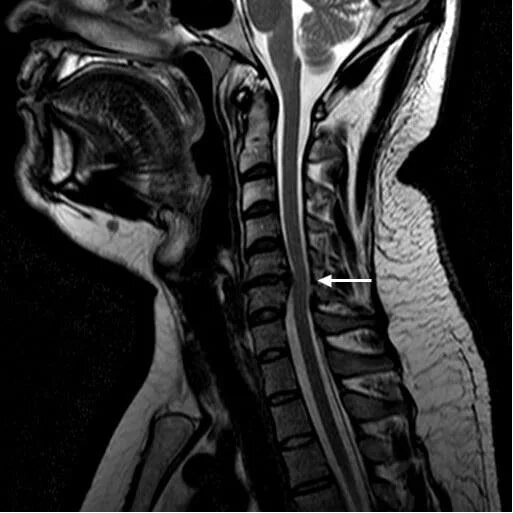

Удалил шейную грыжу